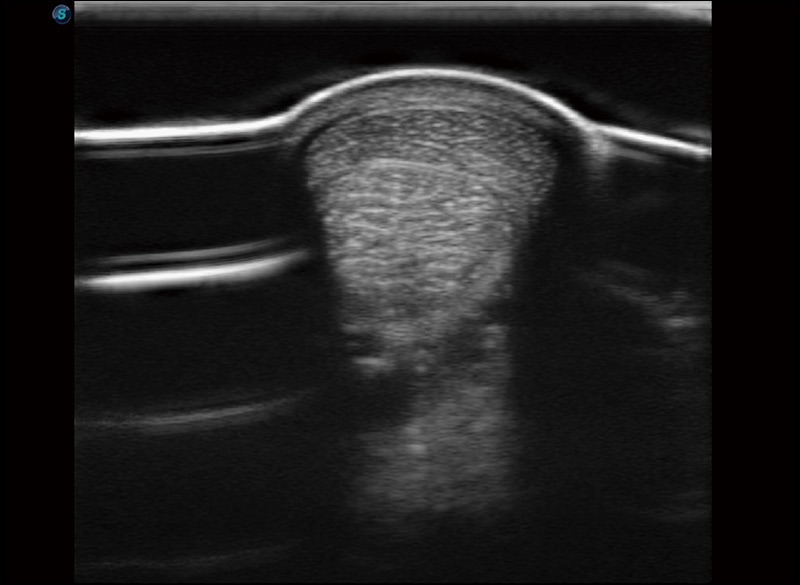

α1卓越的图像质量和便捷的工作流程,使每位宠物医生都能轻松扫查。其全面的兽用应用功能和紧凑型的结构设计,可以满足动物检查的多种需要。专业的预设检查模式和多领域测量软件包有助于为不同类型的动物提供检查, 让宠物医生能够出色的完成工作。

任意波束合成技术

在不牺牲时间分辨率的情况下提供出色的图像

空间复合成像

优化不同角度的图像